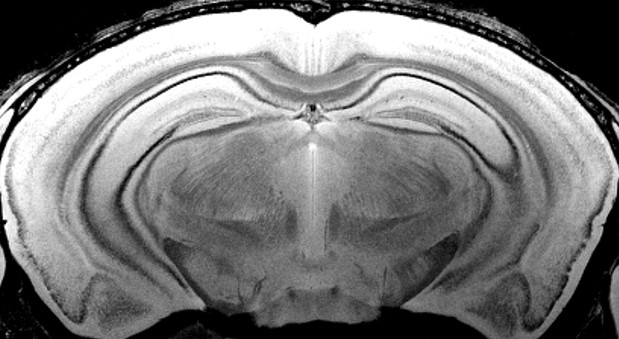

Impactful preclinical neuroscience studies require the most relevant models and study design. Such studies often demand a larger degree of physical freedom, be it due to the size of the species under investigation or the necessity of extra room for extensive peripherals. With a field-strength of 7 Tesla combined with 40 cm of bore space, the BioSpec 70/40 provides increased sensitivity for highest resolutions with maximal space to enable studies that are perfectly designed for your research.

In addition to gradient inserts for optimal scanning of small rodents, the BioSpec 70/40 facilitates non-human primate studies with specially designed animal monitoring and handling provisions as well as accessories for awake studies.